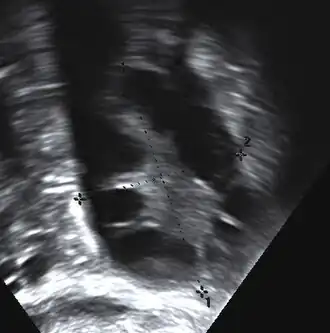

Gynecologic ultrasonography first looks for small ovarian follicles.[75] To count as polycystic ovaries, at least 20 follicles need to be present, smaller than 9 mm. This used to be 12 in older diagnostic criteria.[16] A less clear marker of PCOS is enlarged ovaries.[75] Ovary need to be at least 10 cm3 to count.[16] For sexually active individuals or those that agree, a transvaginal ultrasound approach is preferred. Alternatively, AMH levels can be tested in the blood.[75] Laparoscopic examination may reveal a thickened, smooth, pearl-white outer surface of the ovary. This would usually be an incidental finding if laparoscopy were performed for some other reason, as it would not be routine to examine the ovaries in this way to confirm a diagnosis of PCOS.[78]